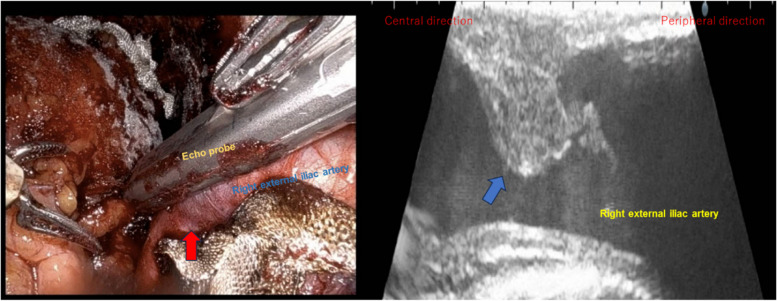

Usefulness of lower extremity pulse oximetry for detection of external iliac artery dissection during robot-assisted radical prostatectomy.